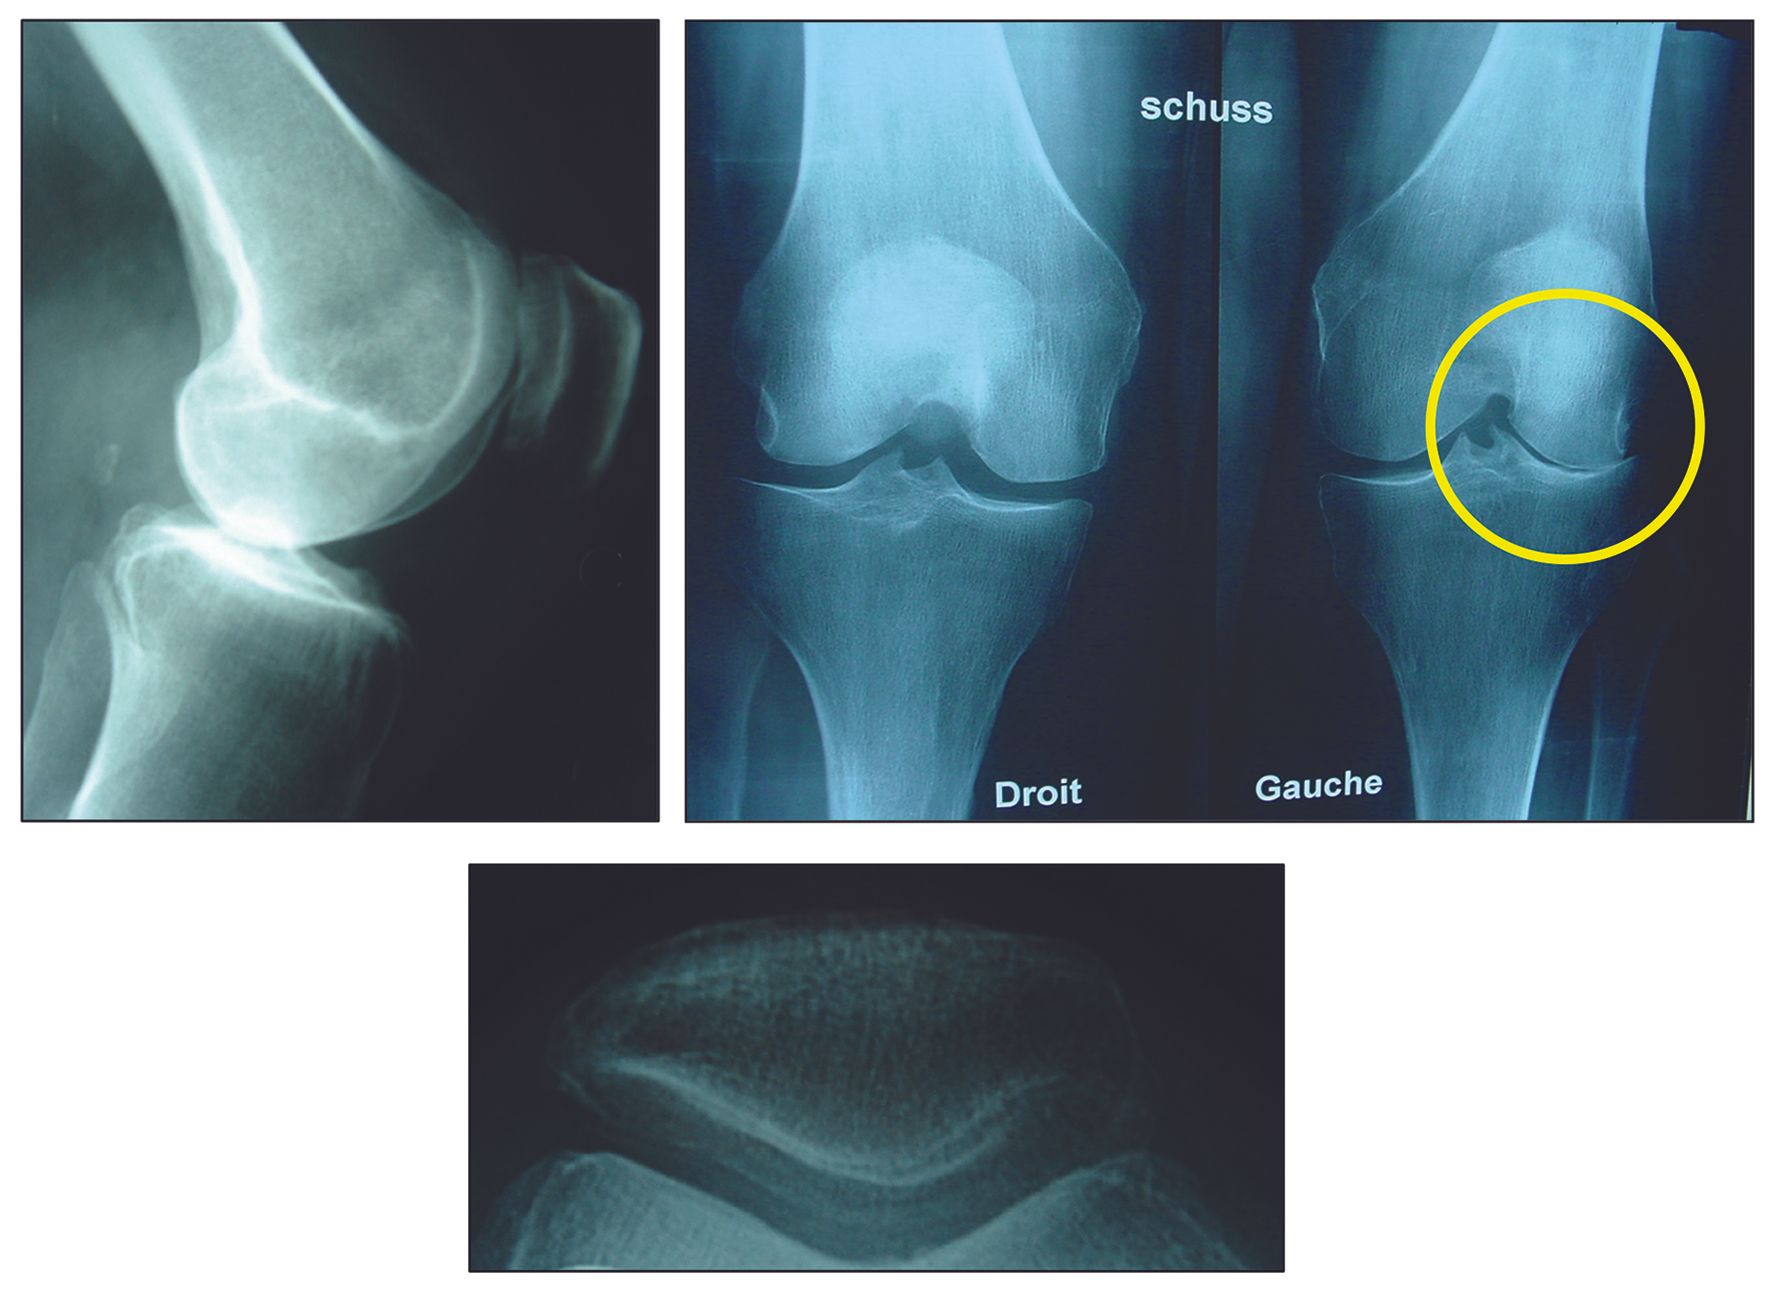

Isolated damage to the lateral tibiofemoral compartment is a determining factor for the indication (Fig. 1). Although usually due to osteoarthritis, damage caused by very localized necrosis of the lateral condyle is also a good indication (Fig. 2). The preoperative deformity should be only moderate, preferably intra articular or epiphyseal, and reducible on stress x-rays.

Some authors do not view moderate asymptomatic patellofemoral injury as a strict contraindication. UKA is possible in this situation if the patient is elderly with low functional expectations.7,15,16 Lateral vertical patellectomy, or patelloplasty with patellar decompression may be offered in addition to UKA to reduce patellofemoral pain (Fig. 4).